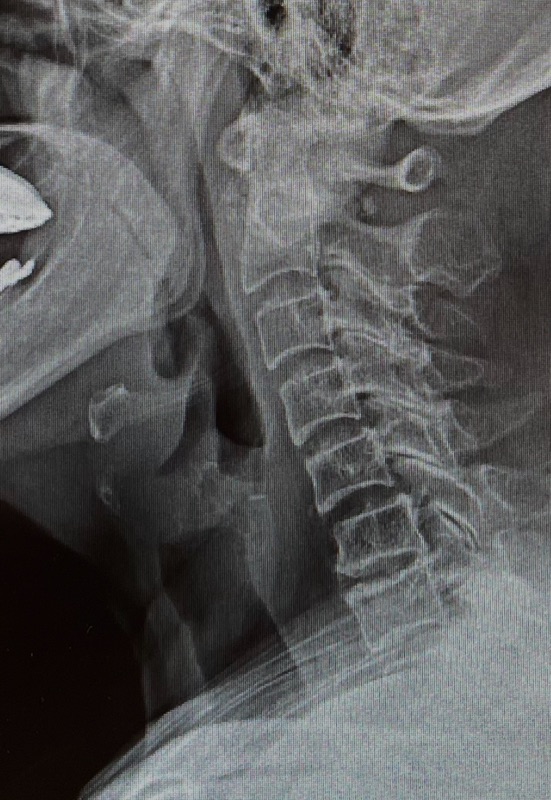

เอกซเรย์ (X-ray): เพื่อดูโครงสร้างกระดูก ดูความแคบของช่องว่างระหว่างกระดูก และดูว่ามีหินปูนเกาะกระดูกหรือไม่